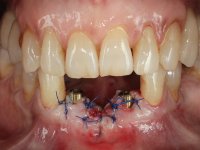

Após estudo imagiológico foi planificada a colocação de dois implantes de 3.3 mm de diâmetro e 10 mm de comprimento. No dia da cirurgia foram extraídos os dentes 42 e 32 e removido o implante. Os implantes foram colocados na zona dos alvéolos tendo o cuidado de lingualizar um pouco o seu posicionamento. Foi feita uma impressão pela técnica de moldeira aberta com o retalho aberto para a confeção da ponte provisória imediata. Enquanto a impressão foi para o laboratório, foram colocados parafusos de cicatrização altos e feita a sutura da ferida cirúrgica. A paciente esperou 2 horas na sala de espera enquanto no laboratório era confecionada a ponte provisória. A ponte provisória imediata aparafusada foi colocada e o seu assentamento controlado imagiologicmente. Passados 3 meses foi realizada a impressão definitiva com uma técnica de moldeira aberta. Nessa consulta aproveitamos para polir a ponte provisória com taças de borracha para que os tecidos moles pudessem maturar em melhores condições. Foi feita a recolha de informação para caracterizar da melhor forma a estrutura monolítica em Zr. Foram utilizadas guias de cor para a cerâmica de tonalidade coronária e gengival. No laboratório foi confecionada uma ponte em Zr. aparafusada que foi cuidadosamente caracterizada. Após aprovação pela paciente foi colocada definitivamente em boca. O aperto foi feito com uma chave dinâmica com 35 N de torque. Os orifícios foram tapados com teflon e obturados com resina composta.